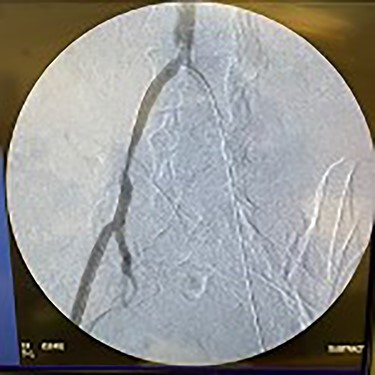

Catheter arteriogram results showed significant occlusion of the left iliac artery (Figs 3 and 4), the right iliac artery (Fig. 1), as well as the distal abdominal aorta (Fig. 2). There were numerous collateral vessels noted, indicating the presence of long-standing proximal stenosis (Fig. 1). The decision was made to use angioplasty to help widen the areas of stenosis. An 8 mm × 40 mm Passeo balloon was advanced from the right femoral artery into the left iliac artery (Fig. 7) and insufflated to 6 mmHg (Fig. 6). The balloon was allowed to remain expanded for 1 min and then was deflated. Next, the distal aorta was repaired in a similar fashion. The balloon was advanced into the distal aorta from the right femoral access and insufflated to 12 mmHg (Fig. 8). The balloon was allowed to remain expanded for 90 s.

Fluoroscopy of right iliac artery showing vast collateral vascular formation, indicating long-standing proximal obstruction.